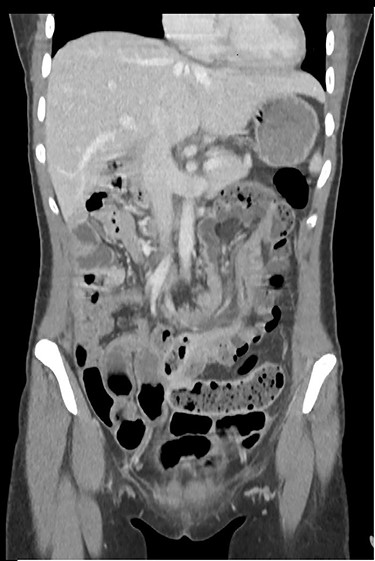

The clinical examination showed a slightly deteriorated condition and a painful distended abdomen with tenderness in all quadrants. There was no rebound pain or palpable masses. Blood tests showed a normal white cell count with a very slight elevation in C-reactive protein (7 mg/l). In the emergency department, the first diagnostic approach with ultrasonography revealed a circular concentric layer, with a maximum diameter of 4–5 cm, highly suspicious of invagination in the left upper quadrant (Fig. 1). The second step was to perform a CT scan with consequent confirmation of the diagnosis. The exam revealed a long ileocolonic intussusception of the ascending colon into the transverse colon, with possible involvement of the terminal ileum; a suspicious strangulation of a superior mesenteric artery branch was postulated (Figs 2 and 3).

CT scan with long ileocolonic intussusception of the ascending colon into the transverse colon, with possible involvement of the terminal ileum, coronal plane.